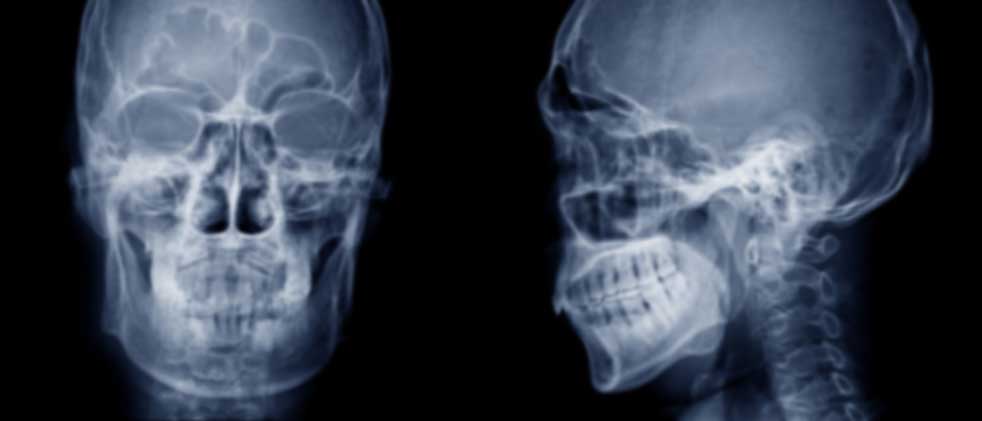

The AO CMF NA community is a multidisciplinary group composed of oral and maxillofacial surgery, otolaryngology, and plastic surgery.